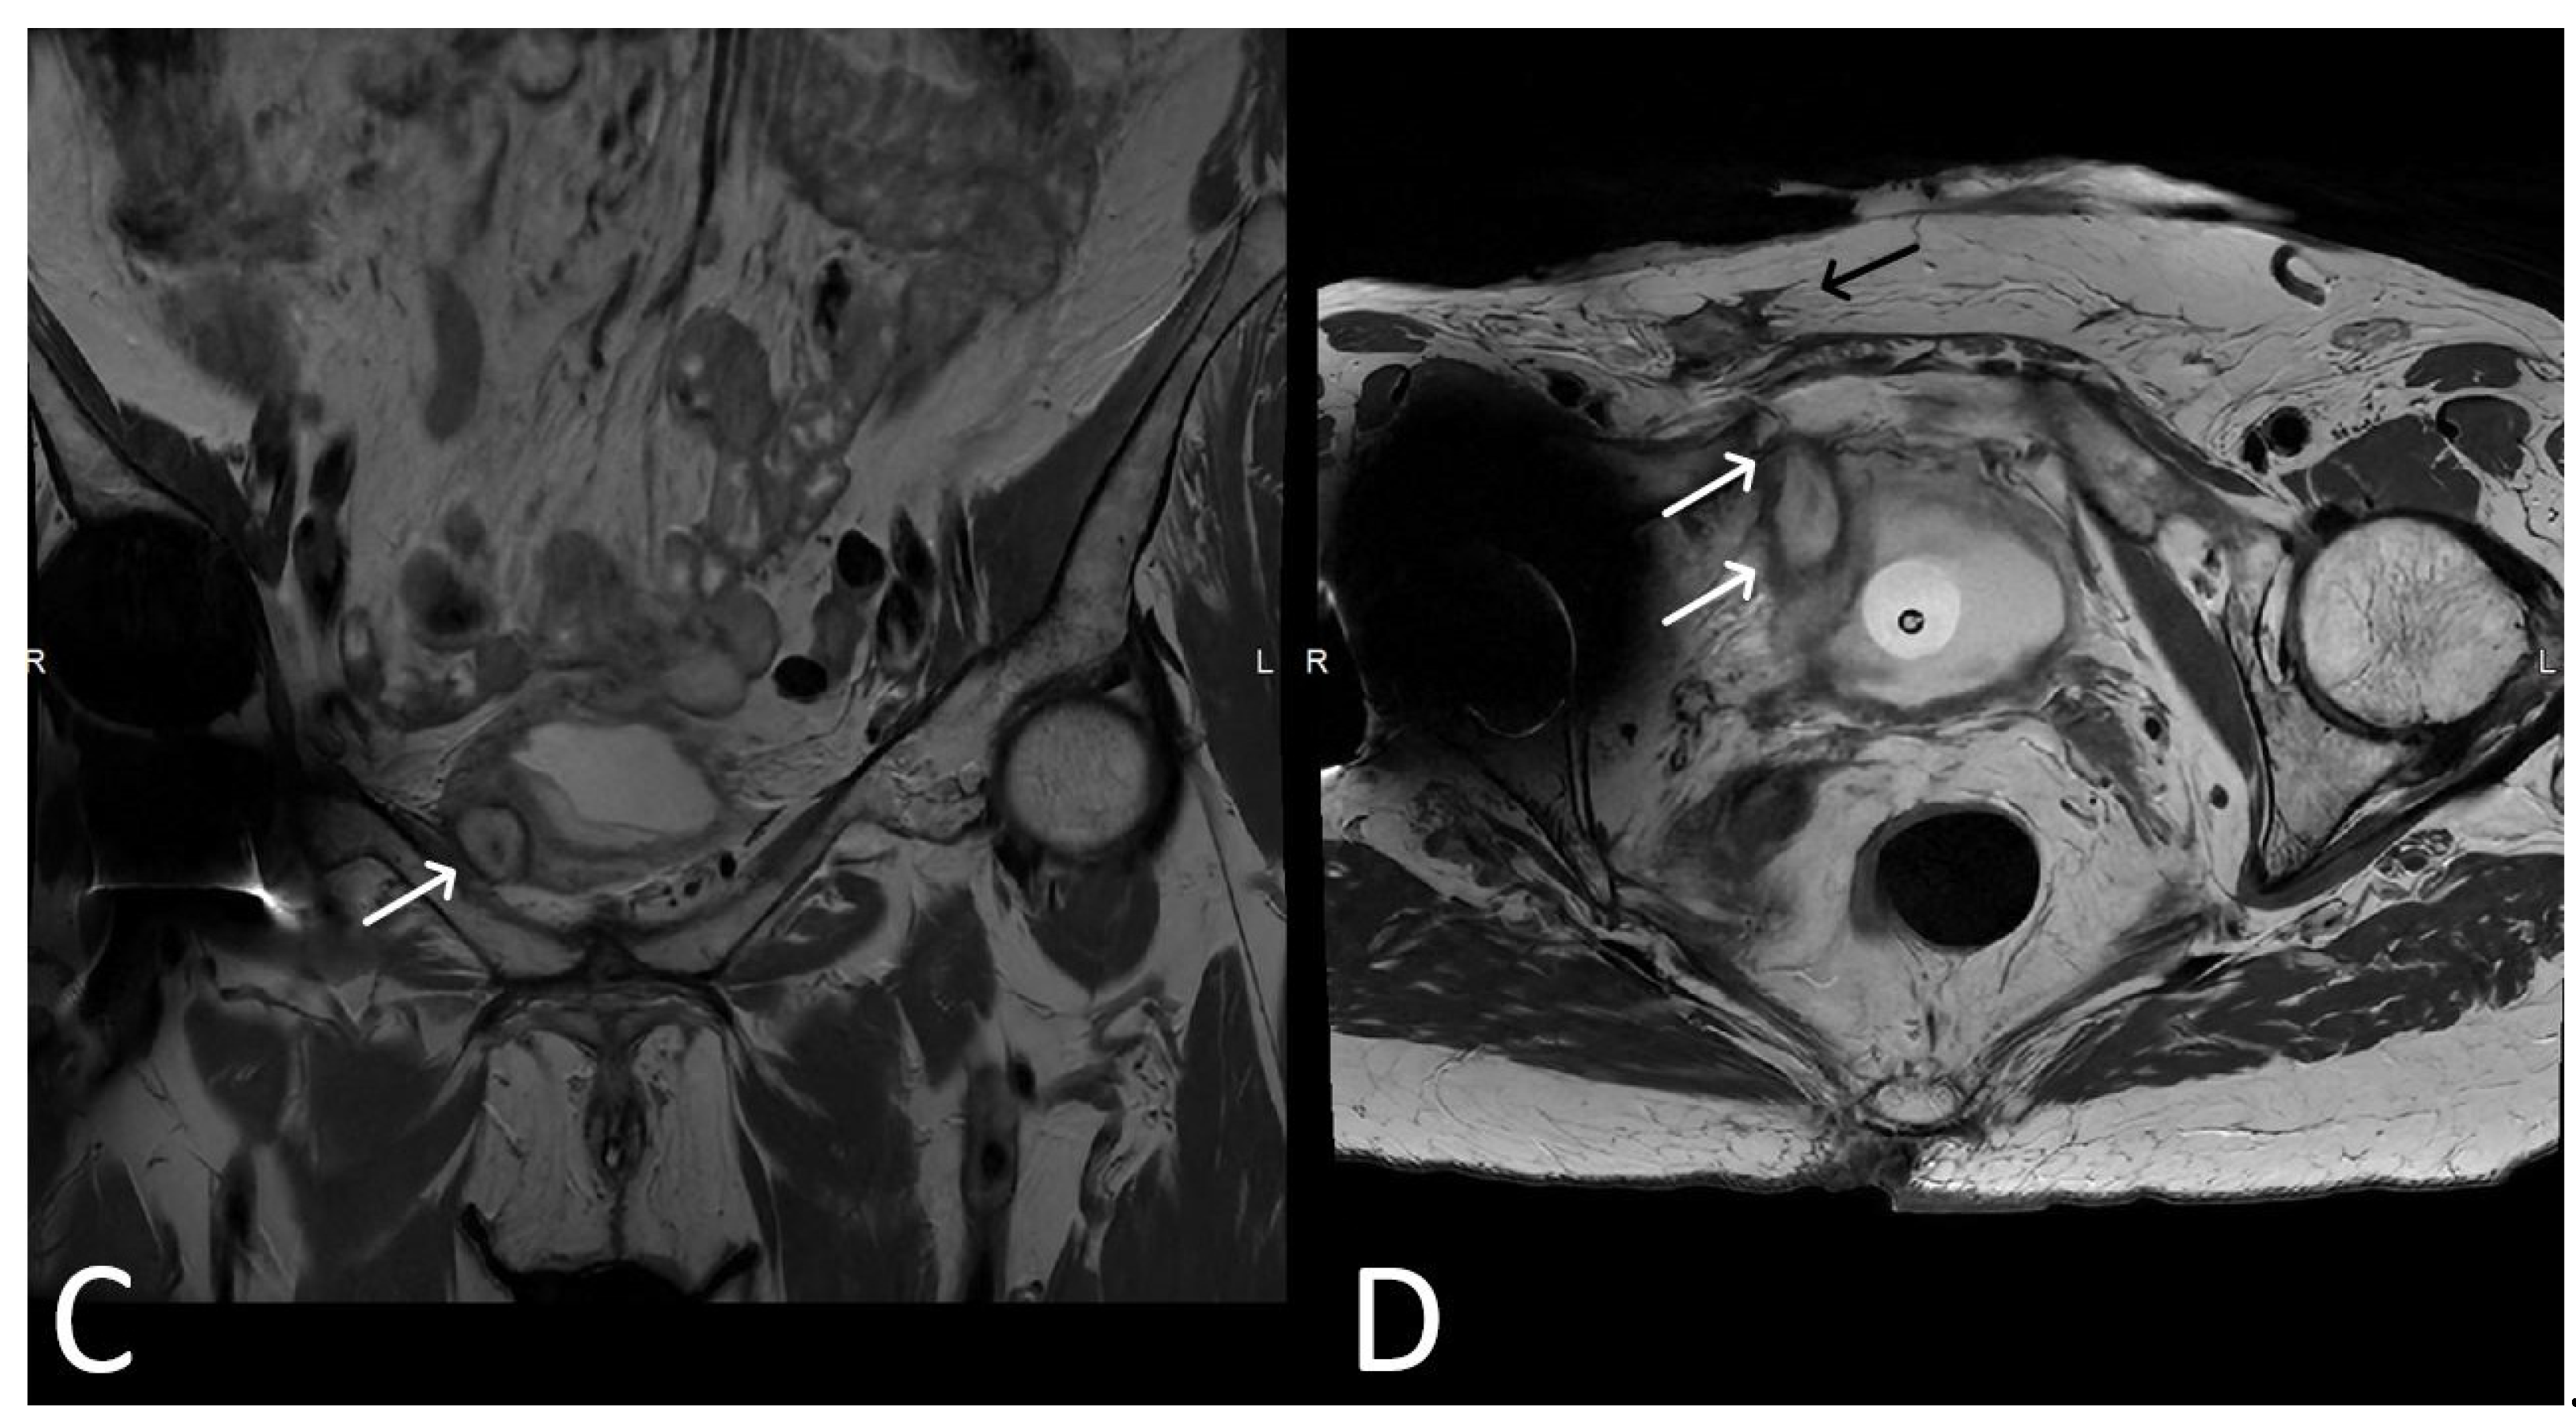

3. Normal Appearance of Urethral Meshes on MRI/CT

4. Urethral Mesh in Oncological Patients